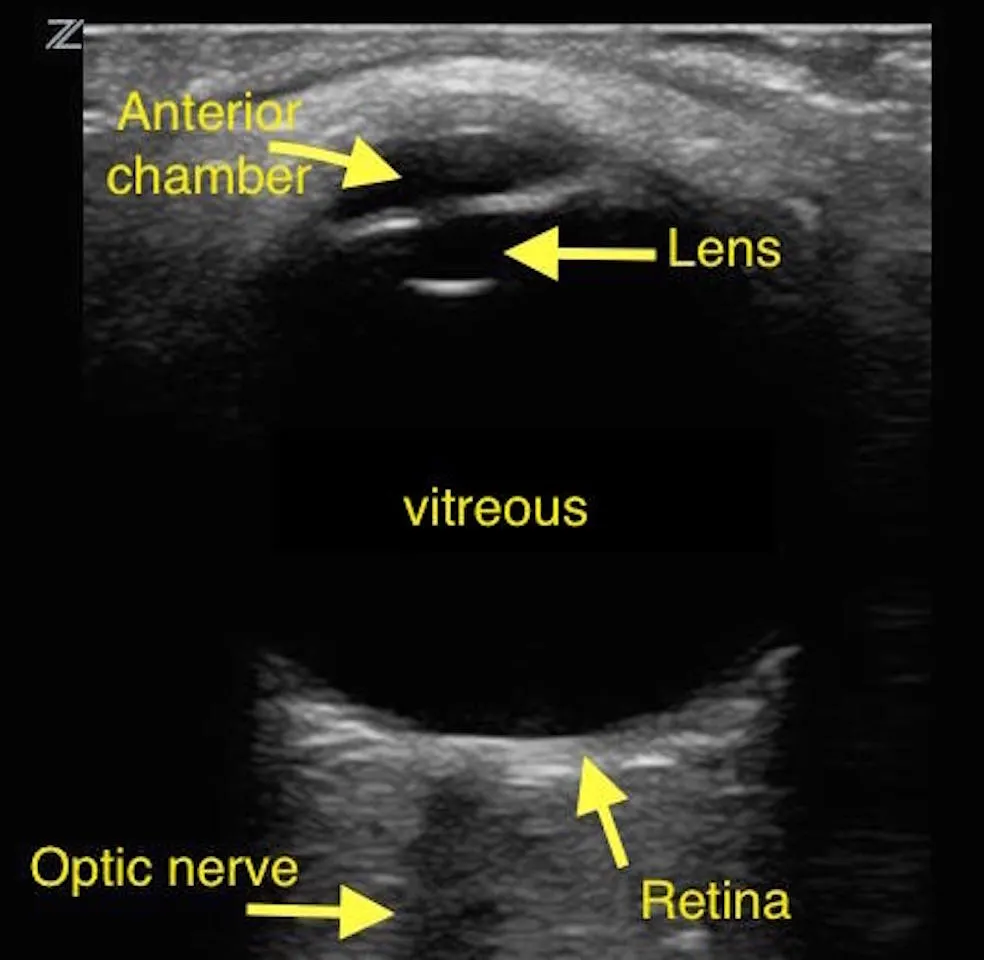

D1. Normal Anatomy